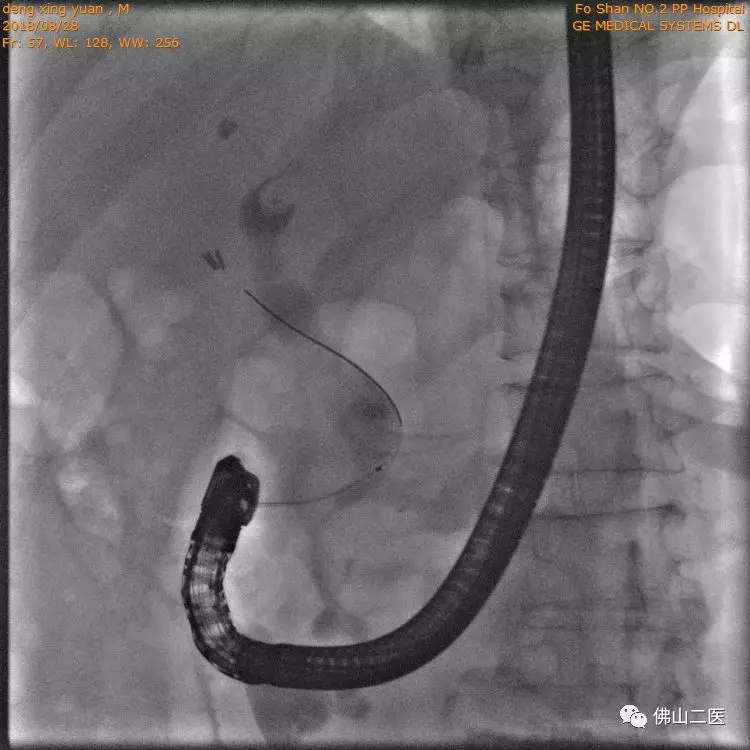

手术中内镜观察到原来肠道被切断后的输入端闭合口(输入攀)

视野下倒置的胆管和胰腺在肠道的开口处(oddi括约肌)